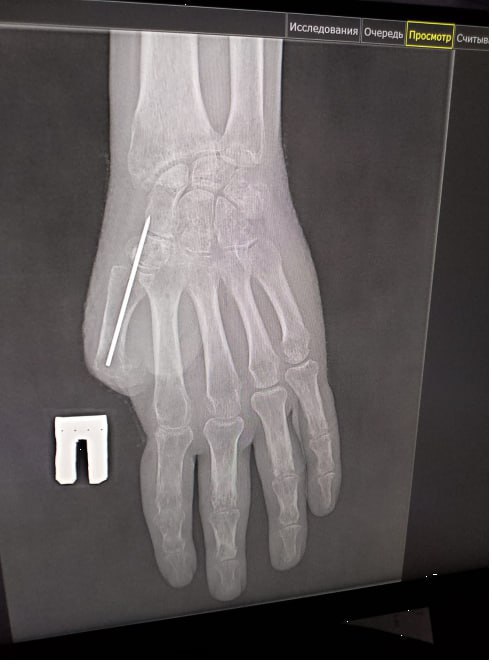

В Прокопьевске в микрохирургическом отделении Прокопьевского ортопедо-хирургического центра проводят кропотливую работу по восстановлению пальца бойца СВО. Об этом рассказал министр здравоохранения Кузбасса Андрей Тарасов.

Мужчина потерял большой палец во время взрыва, однако доктора пытаются вернуть руку в прежний вид. С начала года пациенту убрали грубые рубцы, сформировали основу для будущего большого пальца.

«В ходе следующей операции специалисты сформировали первый луч кисти и выполнили пластику «китайским лоскутом» – пересадили на кисть лоскут ткани с собственными сосудами», — заявил министр.

Таким образом у мужчины будет полноценное кровоснабжение и надежное приживление пальца. Скоро бойца ждет коррекцию прижившегося лоскута и углубление межпальцевого промежутка, что придаст кисти еще больше функциональности и естественный вид.